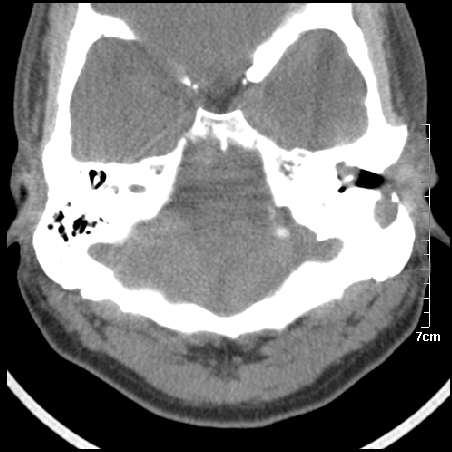

病例2

m/27

胆脂瘤是是以鳞状上皮内衬充满角质化碎片的囊,随着角化屑片的不断堆积,肿块逐渐增大,胆脂瘤可为先天性(2%)或后天性(98%)。胆脂瘤有感染史。中耳内的鳞状上皮通常有外耳道的上皮通过一鼓膜的缺损移行至中耳,其他的原因包括鳞状上皮化生。由于欧氏管的功能不全所引起的中耳负压可产生上鼓室鼓膜松弛部的牵引性开袋。继而发展成胆脂瘤。成年人胆脂瘤时乳突常发育差,而儿童常有广泛性乳突气化,这种气化可导致胆脂瘤的更广泛的乳突扩散。后天性胆脂瘤患者大多数存在骨质破坏。

松弛部胆脂瘤有中央性穿孔或后上部牵引口袋所致。紧张部胆脂瘤经常侵蚀听小骨并引起传导性耳聋。

中耳胆脂瘤有两个重要并发症:一是面神经管的水平段受暴露,二是外侧半规管受侵蚀产生瘘管。面神经在ct上难以显示或不可能显示,除非其周围有空气包绕或有良好轮廓的骨性覆盖。胆脂瘤还可合并感染,产生于急性中耳炎.乳突炎所描述的那些合并症。